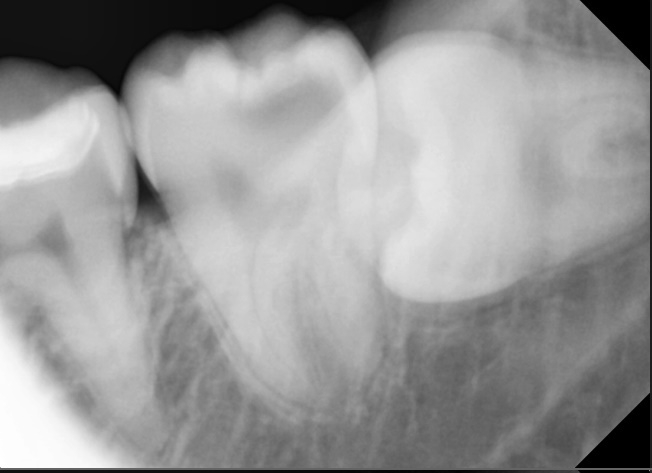

둘째, 충치가 신경 가까이까지 깊게 진행되어 있었습니다.

단순히 충치만 제거하면 신경이 노출될 가능성이 높아졌습니다.

충치가 신경 가까이까지 진행되어 있었기에 일반적인 치료만으로는 신경 손상 가능성이 높았습니다.

그래서 MTA 부분신경치료를 진행했습니다.